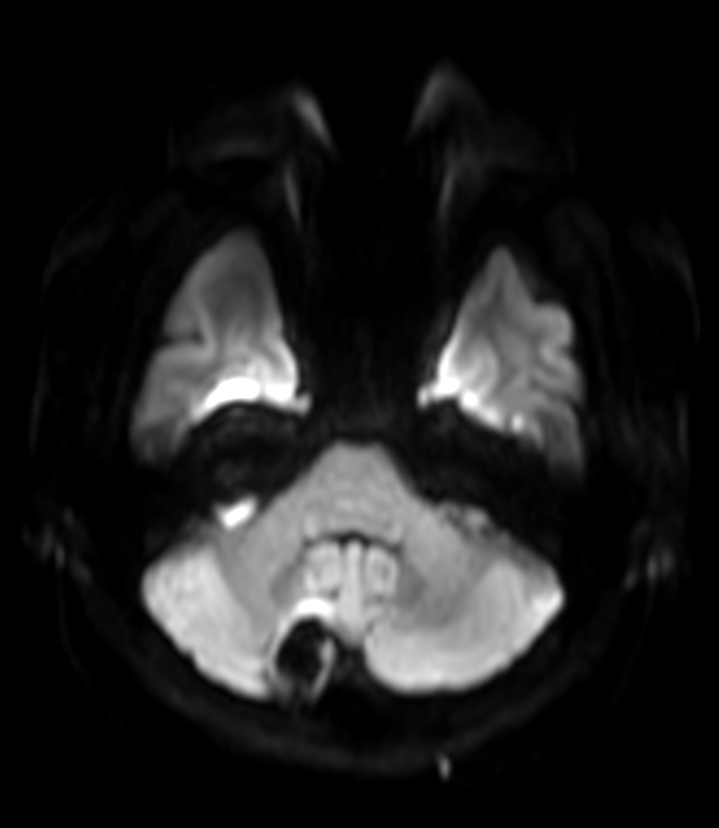

DTI b800 MultiBand SENSE 32 directions

DTI b800 MultiBand SENSE 32 directions (FA map)